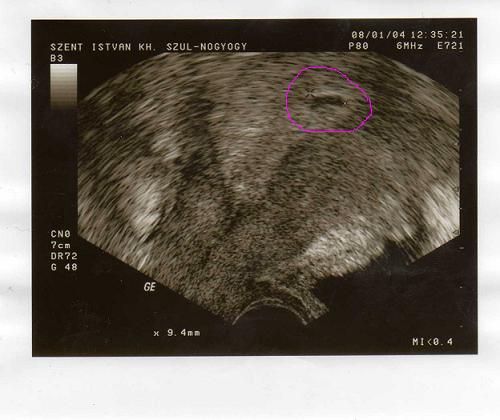

csütörtökön, azaz 3-án voltam újra ultrahangon. a leletem szerint CRL 8mm, azaz gondolom, hogy már ilyen "nagy", 1 embrió és jó szívműködés... ja, és grav.s. 6, úgyhogy ebből azt vettem le, hogy 6 hetes a baba, vagyis 8 hetes terhes vagyok. sajnos pontos adatokat még nem tudok, mert a ciklusom hossza nagyon változó, úgyhogy nem tudom, hogy pontosan melyik napon lehetett a fogamzás.